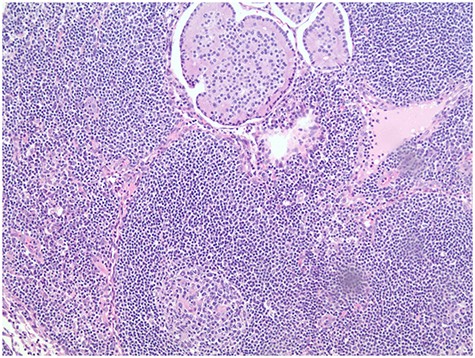

Ampullary well-differentiated, low-grade (G1) neuroendocrine tumor (a); Synaptophysin staining in immunohistochemistry (b).

The patient underwent esophagogastroduodenoscopy (EGD) and endoscopic ultrasound with fine-needle aspiration (FNA), revealing a 21 × 17 mm polypoid ampullary mass causing biliary and pancreatic duct obstruction (Fig. 1). FNA biopsy initially came back as polypoid duodenitis. The patient was referred for endoscopic submucosal dissection where a 20-mm submucosal mass was found in the papilla major and removed. Pathology came back for well-differentiated, low-grade G1 (based on 2010 WHO Criteria) 1.1-cm ampullary neuroendocrine tumor staining with a positive posterior margin (Fig. 2).